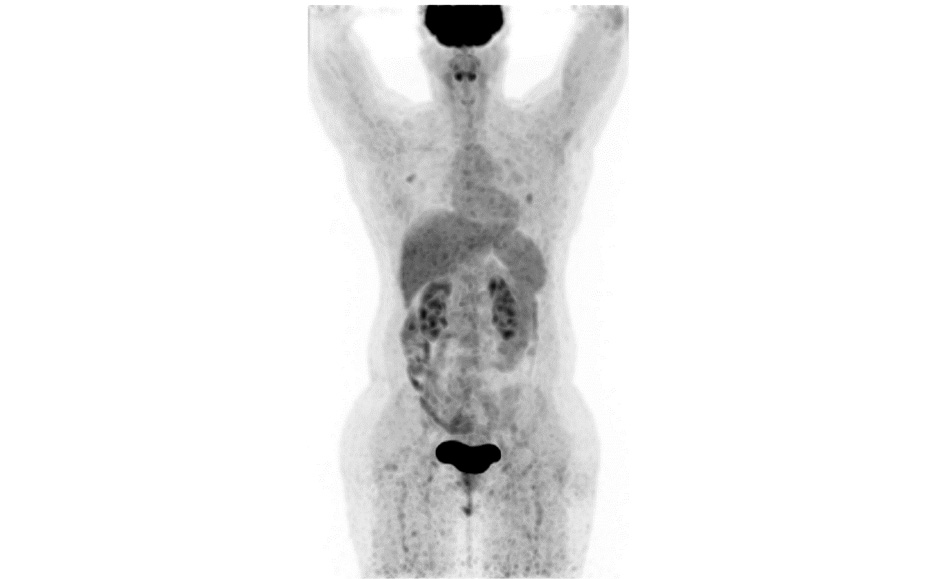

Пациентка №5 43 лет. Рак правой молочной железы, люминальный B, HER2-положительный (ИГХ 3+), исходно метастатический с января 2019 г. (кости, печень, легкие). Значимой сопутствующей патологии нет. Пациентка получила 5 линий лекарственной терапии с января 2019 по март 2022 г., включая все зарегистрированные на территории РФ анти-HER2-препараты – трастузумаб, пертузумаб, трастузумаб эмтанзин, лапатиниб. После 3 проведенных курсов терапии препаратом трастузумабом дерукстеканом зарегистрирован частичный ответ (90%) по критериям RECIST 1.1 (рис. 4, 5). Терапия продолжается по настоящее время, сохраняется частичный ответ. Отдельно следует отметить, что у данной пациентки по логистическим причинам терапия дважды прерывалась более чем на 1,5 мес, что в конкретном случае не повлекло за собой прогрессирования заболевания.

Рис. 4. Пациентка №5, позитронно-эмиссионная томография с компьютерной томографией с 18F-фтордезоксиглюкозой (ПЭТ КТ с 18-ФДГ) – апрель 2022 г., до начала терапии.

Fig. 4. Patient No.5, positron emission tomography with computed tomography with 18F-fluorodeoxyglucose; April 2022, before the therapy.